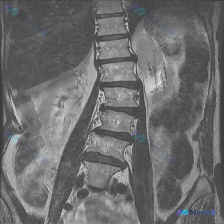

影像核心表现(仅基于提供的T1序列):

- 脊柱力线:明显腰椎侧凸,向右侧弯

- 椎间隙:下腰椎(L4-L5、L5-S1为主)不对称变窄,凹侧(左侧)更明显

- 椎体:边缘可见骨质增生(骨赘)

- 骨髓信号:椎体内部信号基本均匀稍高(脂肪信号),未见明显局灶性低信号灶

- 软组织:椎旁肌左右不对称

- 小关节:部分节段间隙窄、增生